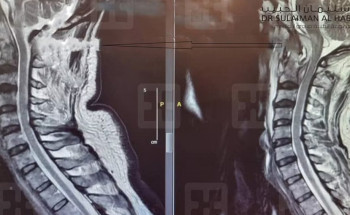

جراحة نادرة ومعقدة بمستشفى سليمان الحبيب بالقصيم تعيد الحركة لستيني عانى من شلل نصفي

في سابقةٍ طبية هي الأولى من نوعها، تمكن فريق طبي بمستشفى الدكتور سليمان الحبيب بالقصيم، من إجراء عملية جراحية ناجحة لرجل عمره (61 عامًا)، عانى من تكوّن صديد "صلب وسائل"، وضاغط بشدة على عنق الدماغ ...